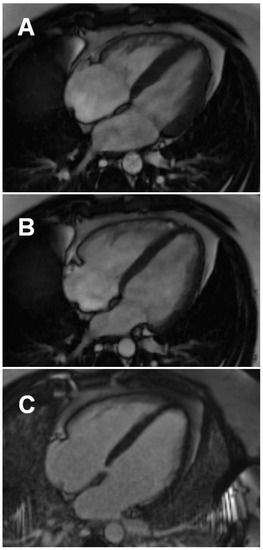

3.3.1. Conventional and LGE Sequences

- Wojtowicz, D.; Dorniak, K.; Ławrynowicz, M.; Rejszel-Baranowska, J.; Fijałkowska, J.; Kulawiak-Gałąska, D.; Szurowska, E.; Koziński, M. Spectrum of lesions visualized in cardiac magnetic resonance imaging in COVID-19-related myocarditis: Findings from a pilot study of the TRICITY-CMR trial. Cardiol. J. 2021, 28, 976–978. [Google Scholar] [CrossRef]